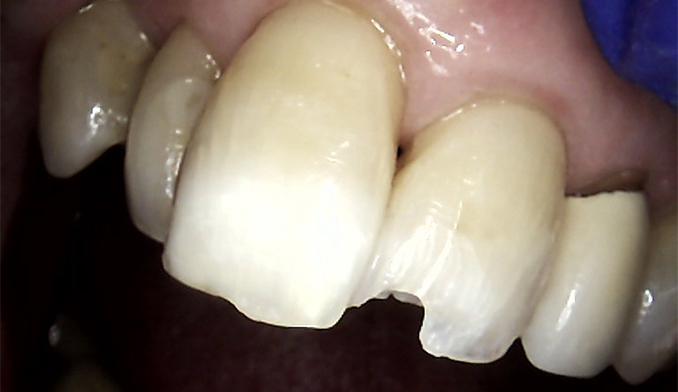

Front Tooth Repair with Bonding

The patient fractured her front tooth. We restored both the appearance and function of the tooth using cosmetic bonding, achieving a natural-looking and durable result.